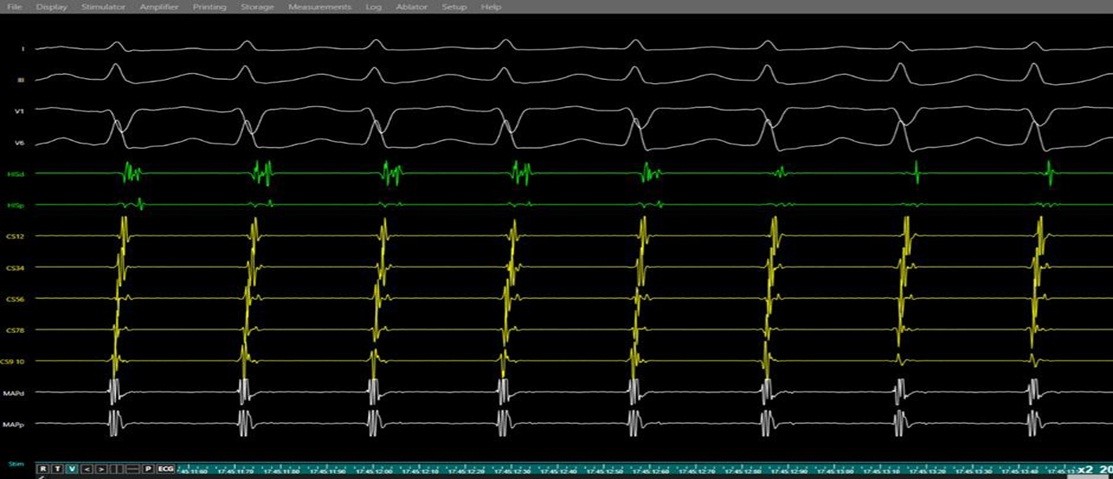

Figure 7. Induction of supraventricular tachycardia (SVT) during electrophysiology study.

Simultaneous surface electrocardiogram (leads I, II, V1, V6) and intracardiac electrograms (His bundle region, and coronary sinus, right ventricle) demonstration of a regular narrow-complex tachycardia with near-simultaneous atrial and ventricular activation and a short VA interval, consistent with typical atrioventricular nodal re-entrant tachycardia.